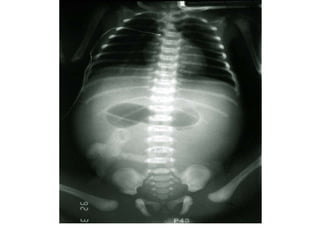

Occlusion du grêle:

niveaux hydroaériques

centraux, plus larges que

hauts, absence d’air dans

le rectum

Occlusion colique

Niveaux hydroaériques périphériques, plus hauts que larges